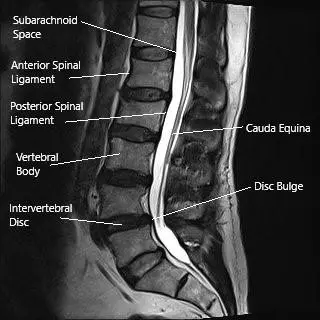

MRI of the lumbar spine in the sagittal section showing disc bulge.